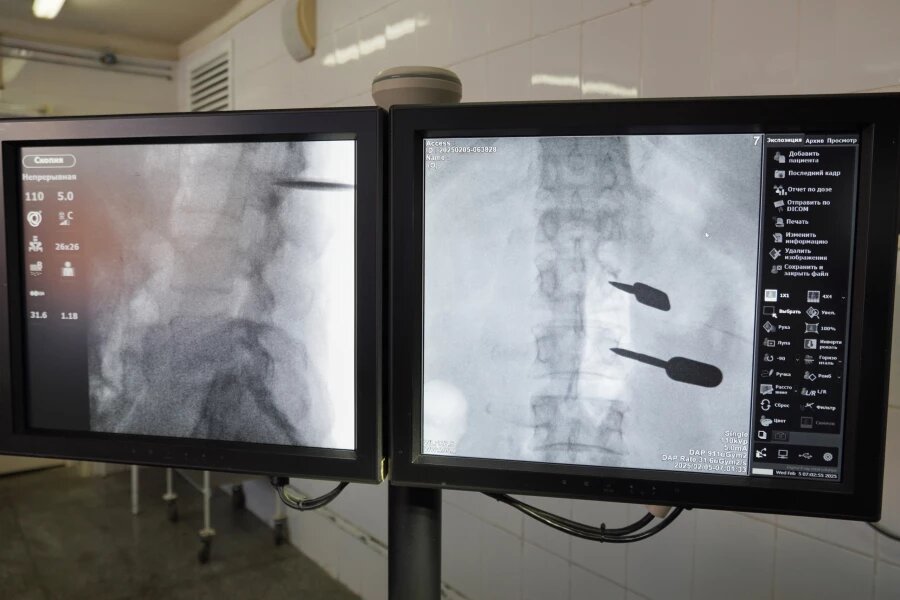

Чтобы больше не терять драгоценное время, врачи приняли решение экстренно оперировать пациента в краевой больнице. Операция проводилась с использованием высоких медицинских технологий.

«Пациенту была выполнена транспедикулярная фиксация с установкой металлоконструкции в поясничный отдел позвоночника. Операция проводилась под общим наркозом и прошла успешно», —.сообщил Евгений Рольгейзер.